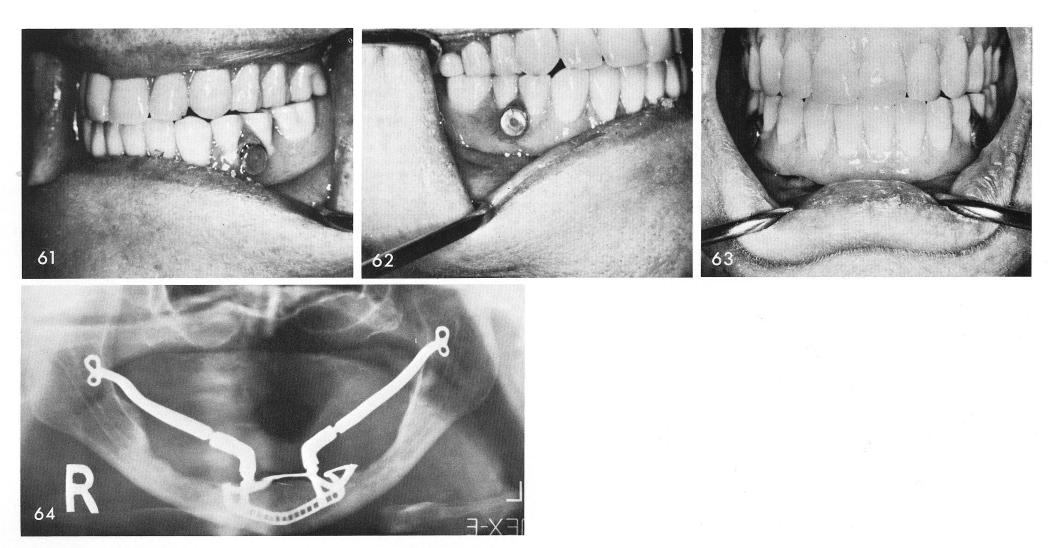

1 Post operative x rays of bilateral sliding cable implants in mandible